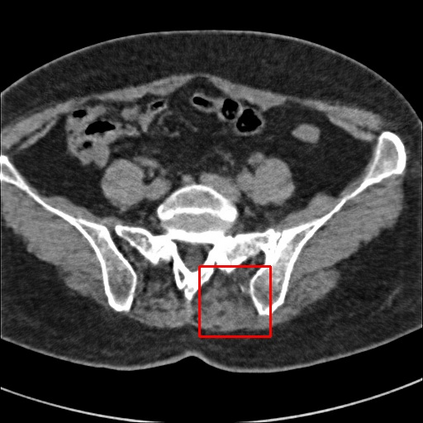

Low-Dose Computed Tomography (LDCT) technique, which reduces the radiation harm to human bodies, is now attracting increasing interest in the medical imaging field. As the image quality is degraded by low dose radiation, LDCT exams require specialized reconstruction methods or denoising algorithms. However, most of the recent effective methods overlook the inner-structure of the original projection data (sinogram) which limits their denoising ability. The inner-structure of the sinogram represents special characteristics of the data in the sinogram domain. By maintaining this structure while denoising, the noise can be obviously restrained. Therefore, we propose an LDCT denoising network namely Sinogram Inner-Structure Transformer (SIST) to reduce the noise by utilizing the inner-structure in the sinogram domain. Specifically, we study the CT imaging mechanism and statistical characteristics of sinogram to design the sinogram inner-structure loss including the global and local inner-structure for restoring high-quality CT images. Besides, we propose a sinogram transformer module to better extract sinogram features. The transformer architecture using a self-attention mechanism can exploit interrelations between projections of different view angles, which achieves an outstanding performance in sinogram denoising. Furthermore, in order to improve the performance in the image domain, we propose the image reconstruction module to complementarily denoise both in the sinogram and image domain.